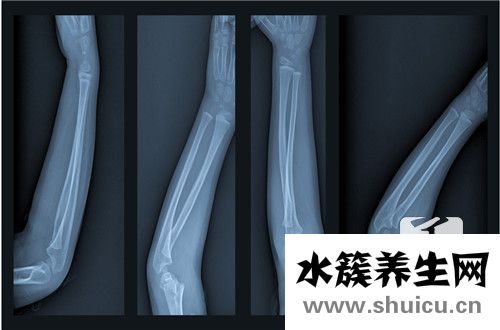

橈骨小頭骨折是普遍的手肘損害,占全身骨折的0.8%,約有l(wèi)/3病人合拼骨節(jié)別的位置損害。橈骨小頭骨折是骨節(jié)內(nèi)骨折,如果有挪動(dòng),理當(dāng)割開復(fù)位內(nèi)固定不動(dòng),修復(fù)解剖學(xué)部位,初期活動(dòng),以修復(fù)腕關(guān)節(jié)伸曲和上臂轉(zhuǎn)動(dòng)作用。

該病由立即外力作用造成的骨折非常少見。普遍的是腕關(guān)節(jié)挺直位跌倒,手掌心碰地,外力作用使橈骨頭出外翻位與肱骨小頭碰撞而造成骨折。常合拼肱骨小頭損害與內(nèi)側(cè)副韌帶損害。常見于成人且非常容易誤診。若不可以獲得早期治療,一些病人上臂轉(zhuǎn)動(dòng)作用受限制,迫不得已將橈骨小頭摘除。

傷后肘兩側(cè)局限發(fā)脹、疼痛,橈骨頭周邊有顯著的壓疼。上臂轉(zhuǎn)動(dòng)活動(dòng)受到限制,處于被動(dòng)活動(dòng)時(shí)疼痛,尤其是在旋后時(shí)顯著。腕關(guān)節(jié)功能問題,伸屈疼痛加劇。依據(jù)Mason分析法可分成三種種類:

I型:橈骨小頭骨折但無挪動(dòng)。骨折線能夠根據(jù)橈骨小頭邊沿或破裂狀,有時(shí)候斜行根據(jù)關(guān)節(jié)面。

Ⅱ型:橈骨小頭骨折并有分離出來挪動(dòng)。骨折塊有尺寸,有時(shí)候小骨折片置入骨節(jié)空隙或礦酸于肱橈關(guān)節(jié)兩側(cè)緣。

Ⅲ型:橈骨小頭粉碎性骨折。橈骨小頭呈破碎狀,挪動(dòng)或無挪動(dòng)。有時(shí)候骨折片呈崩裂狀向周邊分離出來挪動(dòng),也是有呈坍塌骨折。

這類三型分析法可以意味著損害水平,并可出示挑選治療方法的根據(jù)。